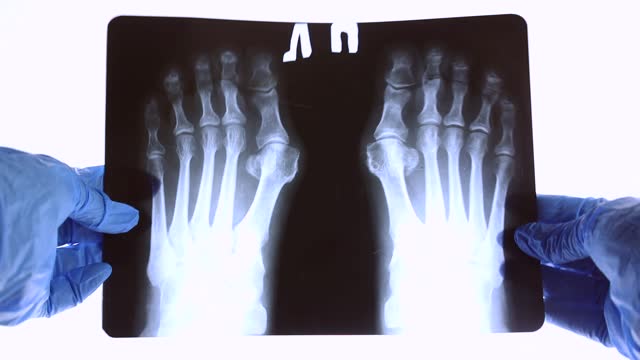

✅무지외반증 통증 아무도 모르는 관리법 8가지

✅무지외반증 통증 관리하는 법

무지 외반증의 심각한 경우에는 전문가 상담을 고려해야 합니다. 물리치료사나 발건강 전문가와 상담하여 적절한 치료 방법을 찾아보세요.

무지 외반증은 초기에 적절한 관리와 운동을 통해 개선할 수 있는 상태입니다.